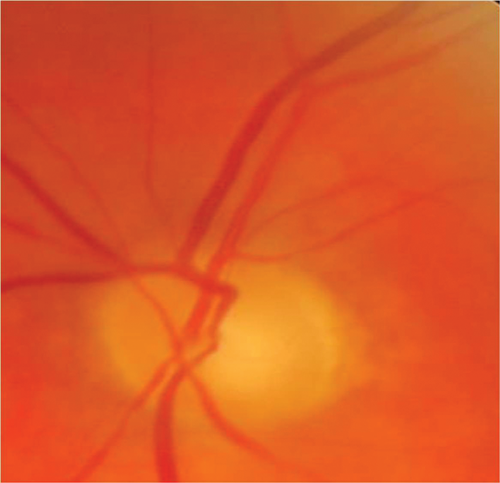

A 30-year-old Caucasian presented with the first episode of unilateral, painless visual loss in one eye upon waking. Crohn’s disease was diagnosed 18 months ago on colonoscopy after a single episode of colitis. She was on no medication. She presented with gross swelling of the optic nerve head on the right and swelling of the left optic nerve head. Vision was 6/36 on the right and 6/9 on the left.

Figure 1 (top and above): Case 2 - right and left fundus.

There was a dense right RAPD, reduction in colour vision, a large, dense unilateral, nasal scotoma, and bilateral mild vitritis. MRI showed no white matter lesions. She was treated with high dose oral steroids with a residual dense nasal field defect and central visual acuity of 6/9. This is an atypical optic neuritis which may be associated with Crohn’s disease. Here the atypical features are the absence of pain, gross optic nerve head swelling and bilateral disease. The presence of intermediate uveitis is consistent with Crohn’s disease. The MRI findings support the likelihood that this pathological process was limited to optic nerve.